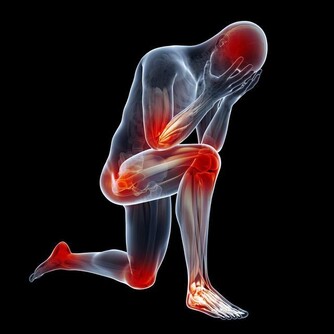

看舌苔,明顯發白,月經量少,顏色黯,有血塊。這都說明體內有寒,是最常見的寒性痛經;像這樣的寒性痛經是最常見的,應該是平時常吃涼東西,冷飲、雪糕、冰激凌、冷麵什麼的;或者,常呆在空調開得很足的環境造成的; 痛經的時候,小肚子冰涼是很常見的,不過,有的人喜按,按一下就舒服多了,這是血虛的表現; 而有的人不敢使勁按,使勁按就很痛,這是血淤的表現; 還有人痛經的時候,小肚子不涼反熱,月經量多、白帶多,那是濕熱型的表現。